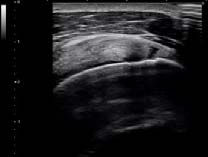

肩腱板断裂 |

超広帯域プローブとこの帯域を最大限利用するためのTriad-THI技術により,体の表層や浅い部位のみならず,診断したい領域全域の高画質化が可能になり,診断精度向上に貢献できると考えている。